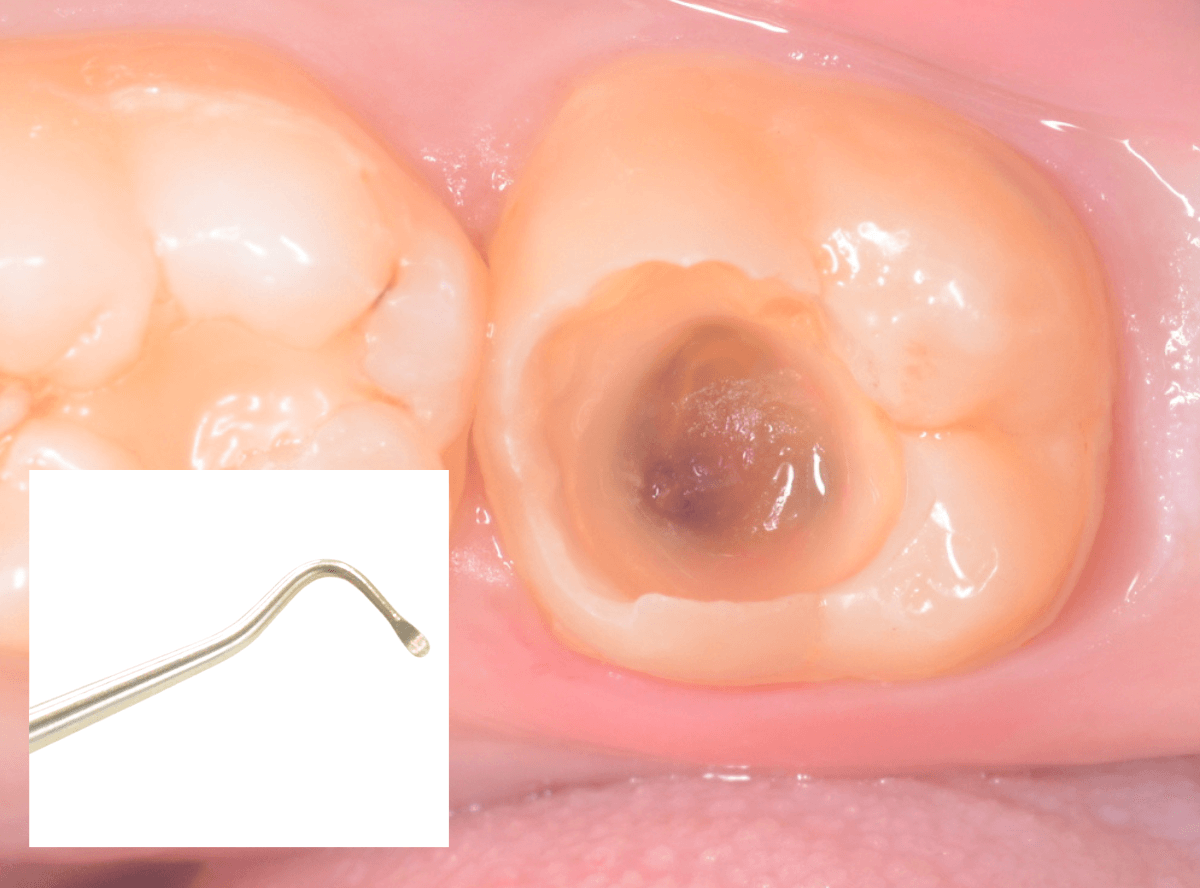

Case.15 レジンの下の深い虫歯

奥歯で咬んだ時に、痛みを感じるという訴えで来院された患者さんです。

パッと見は特に問題なさそうな状態ですが、大きなレジン治療がしてあり、レジンの奥もボヤっと黒っぽく見えてアヤシイ感じです。

麻酔をして、レジンを外します。

レントゲン写真から想定できるような大きな虫歯ですね。

慎重に虫歯を除去します。

赤く染色されている部分が虫歯の残っている部分です。

全ての虫歯を除去したところです。

何とか神経の寸前で虫歯を食い止める事ができましたが、まれに症状が出る事もありますのでお薬をつめてしばらく経過観察します。